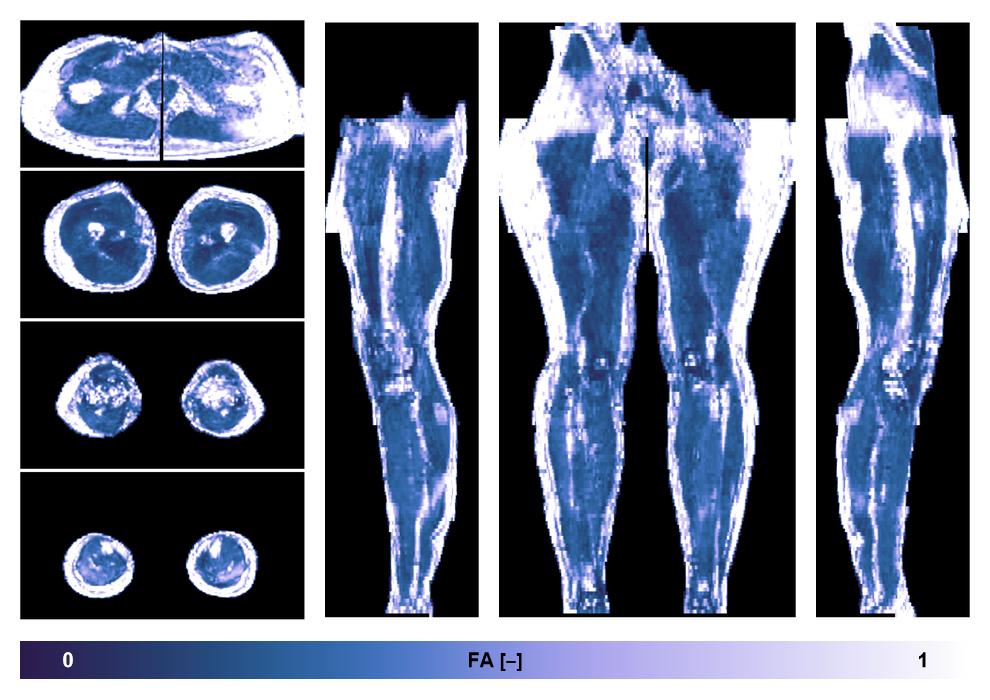

• Fractional anisotropy

IVIM corrected whole leg muscle fractional anisotropy obtained from diffusion tensor imaging.